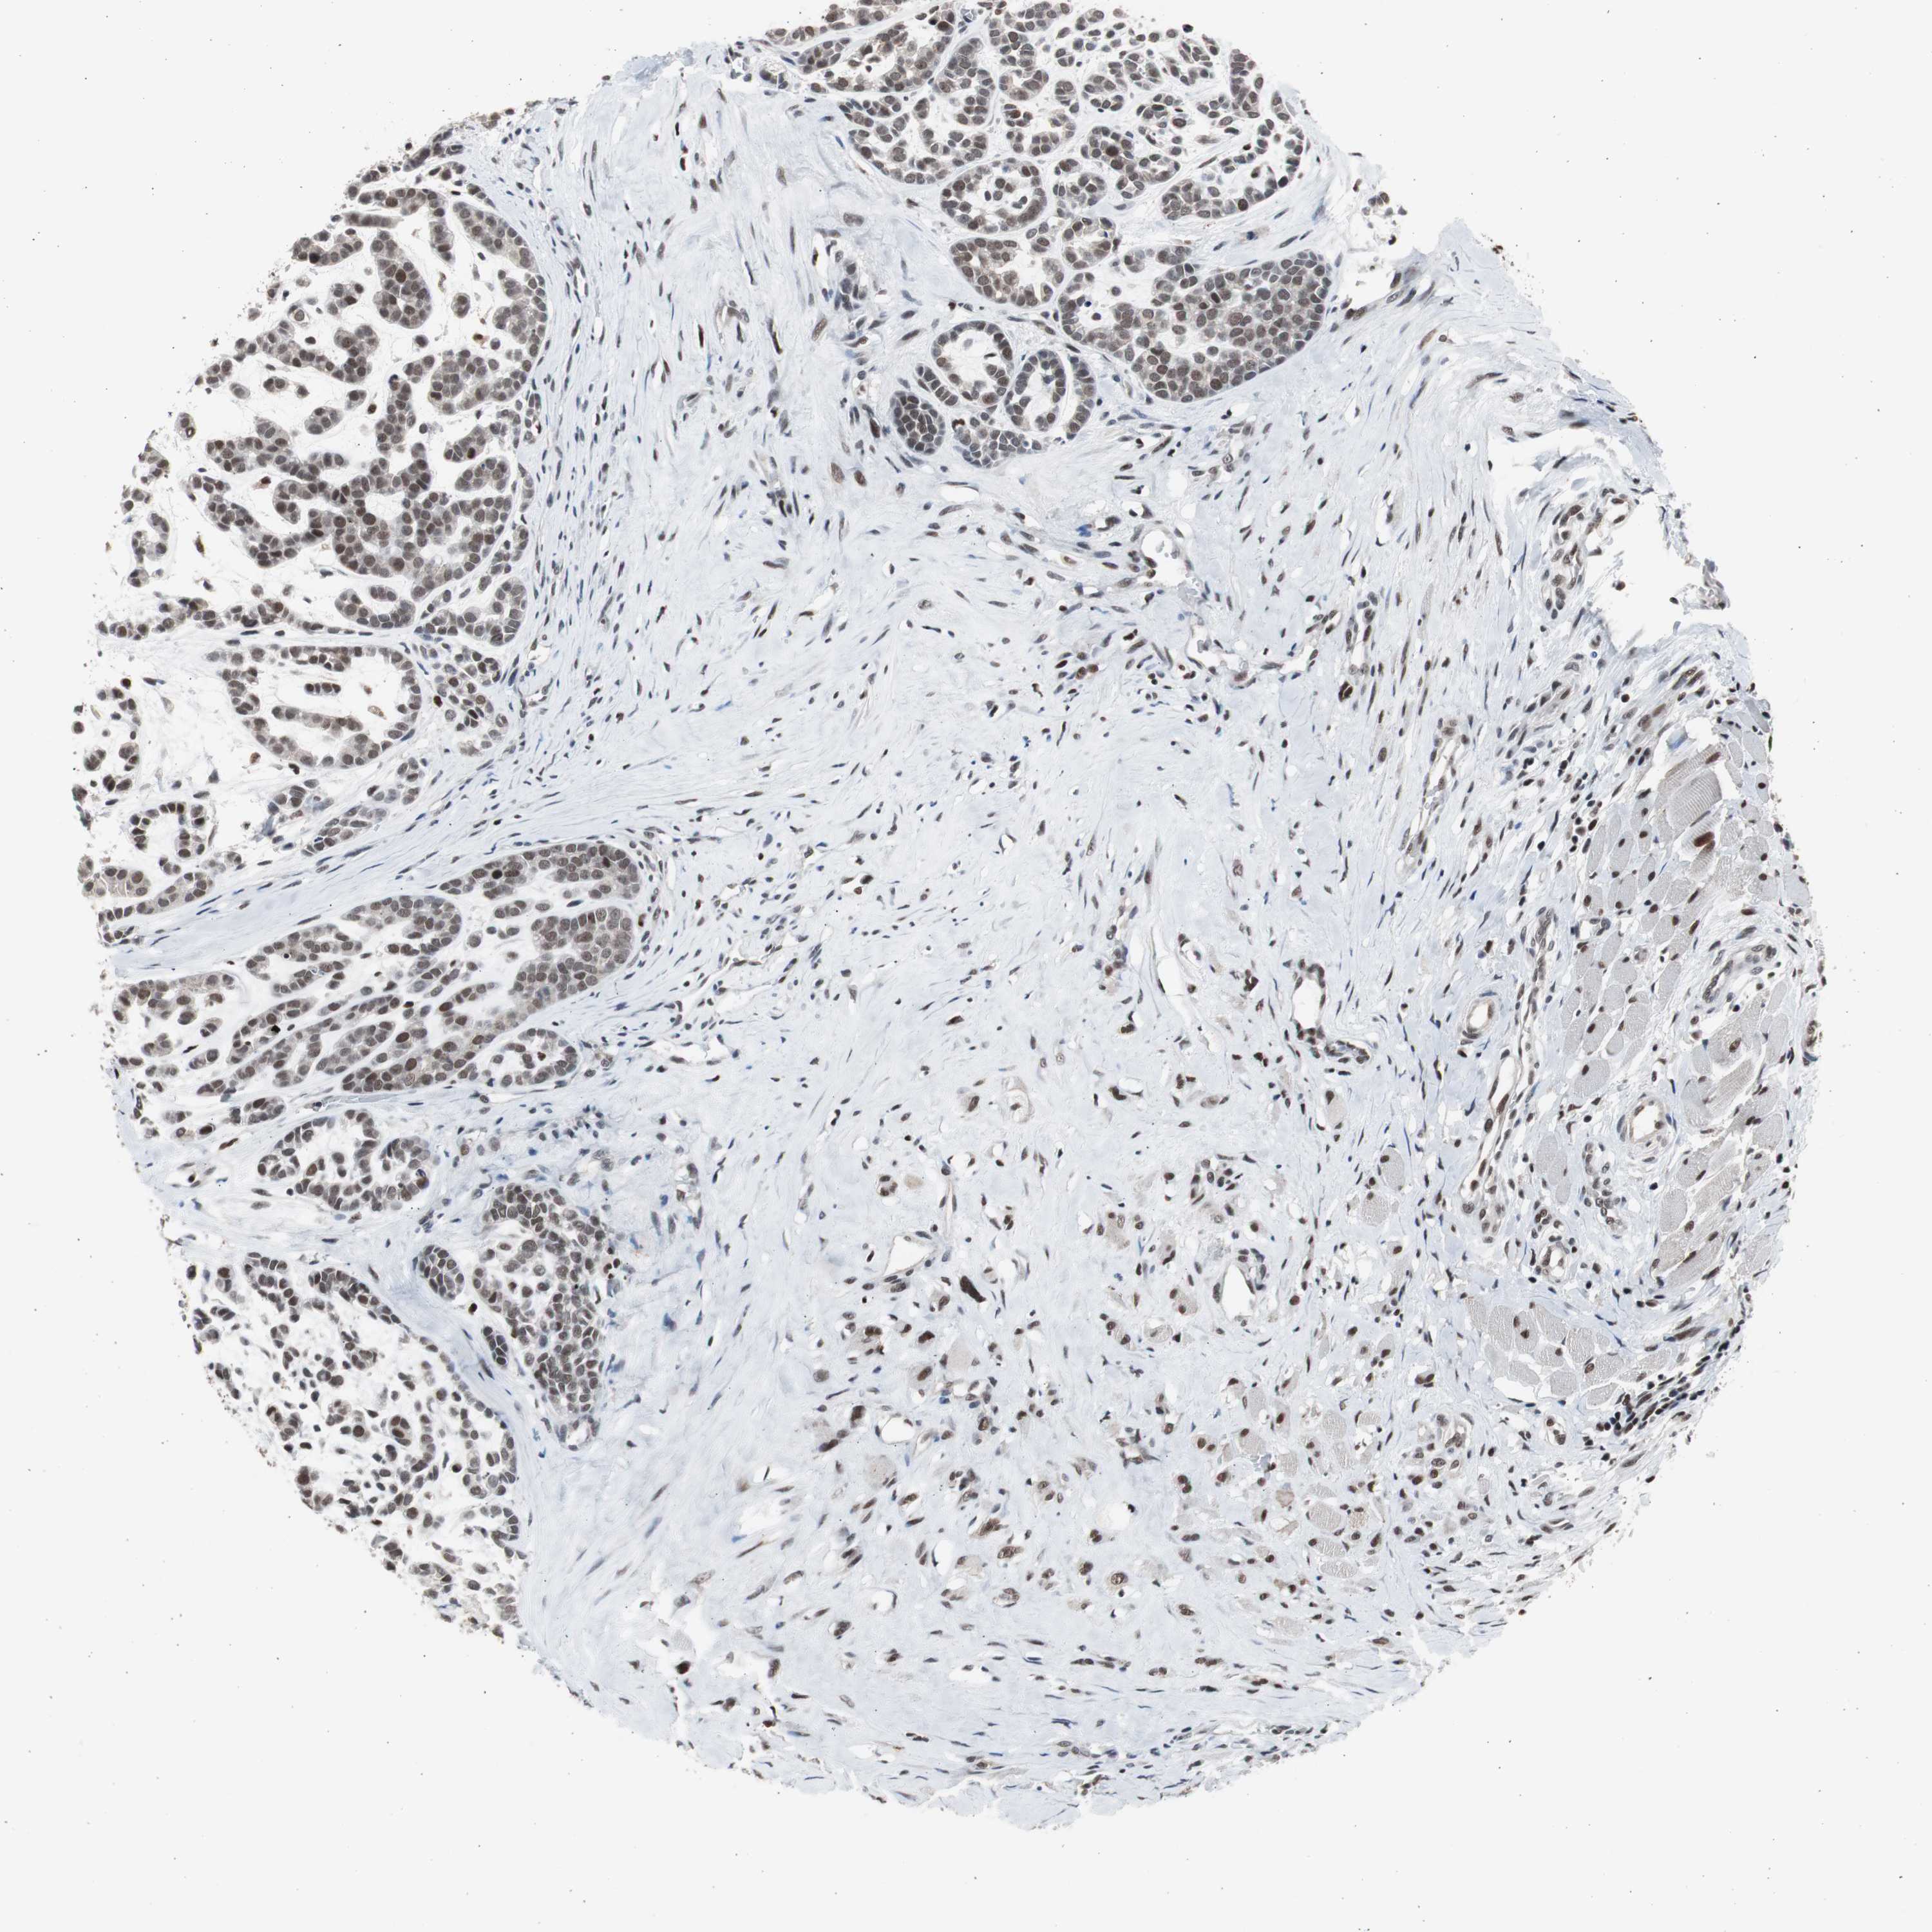

HEAD AND NECK CANCER - Protein expressioni

A mouse-over function shows sample information and annotation data. Click on an image to view it in a full screen mode. Samples can be filtered based on level of antibody staining by selecting one or several of the following categories: high, medium, low and not detected. The assay and annotation is described here.

Antibody stainingi

Antibody staining in the annotated cell types in the current human tissue is reported as not detected, low, medium, or high, based on conventional immunohistochemistry profiling in selected tissues. This score is based on the combination of the staining intensity and fraction of stained cells.

Each image is clickable and will lead to virtual microscopy that enables deeper exploration of all samples and also displays staining intensity scores, fraction scores and subcellular localization as well as patient and tissue information for each sample.

Antibody HPA006914

Staining

High

Medium

Low

Not detected

Intensity

Strong

Moderate

Weak

Negative

Quantity

>75%

75%-25%

<25%

None

Location

Nuclear

Cytoplasmic/membranous

Cytoplasmic/membranous,nuclear

Squamous cell carcinoma, NOS